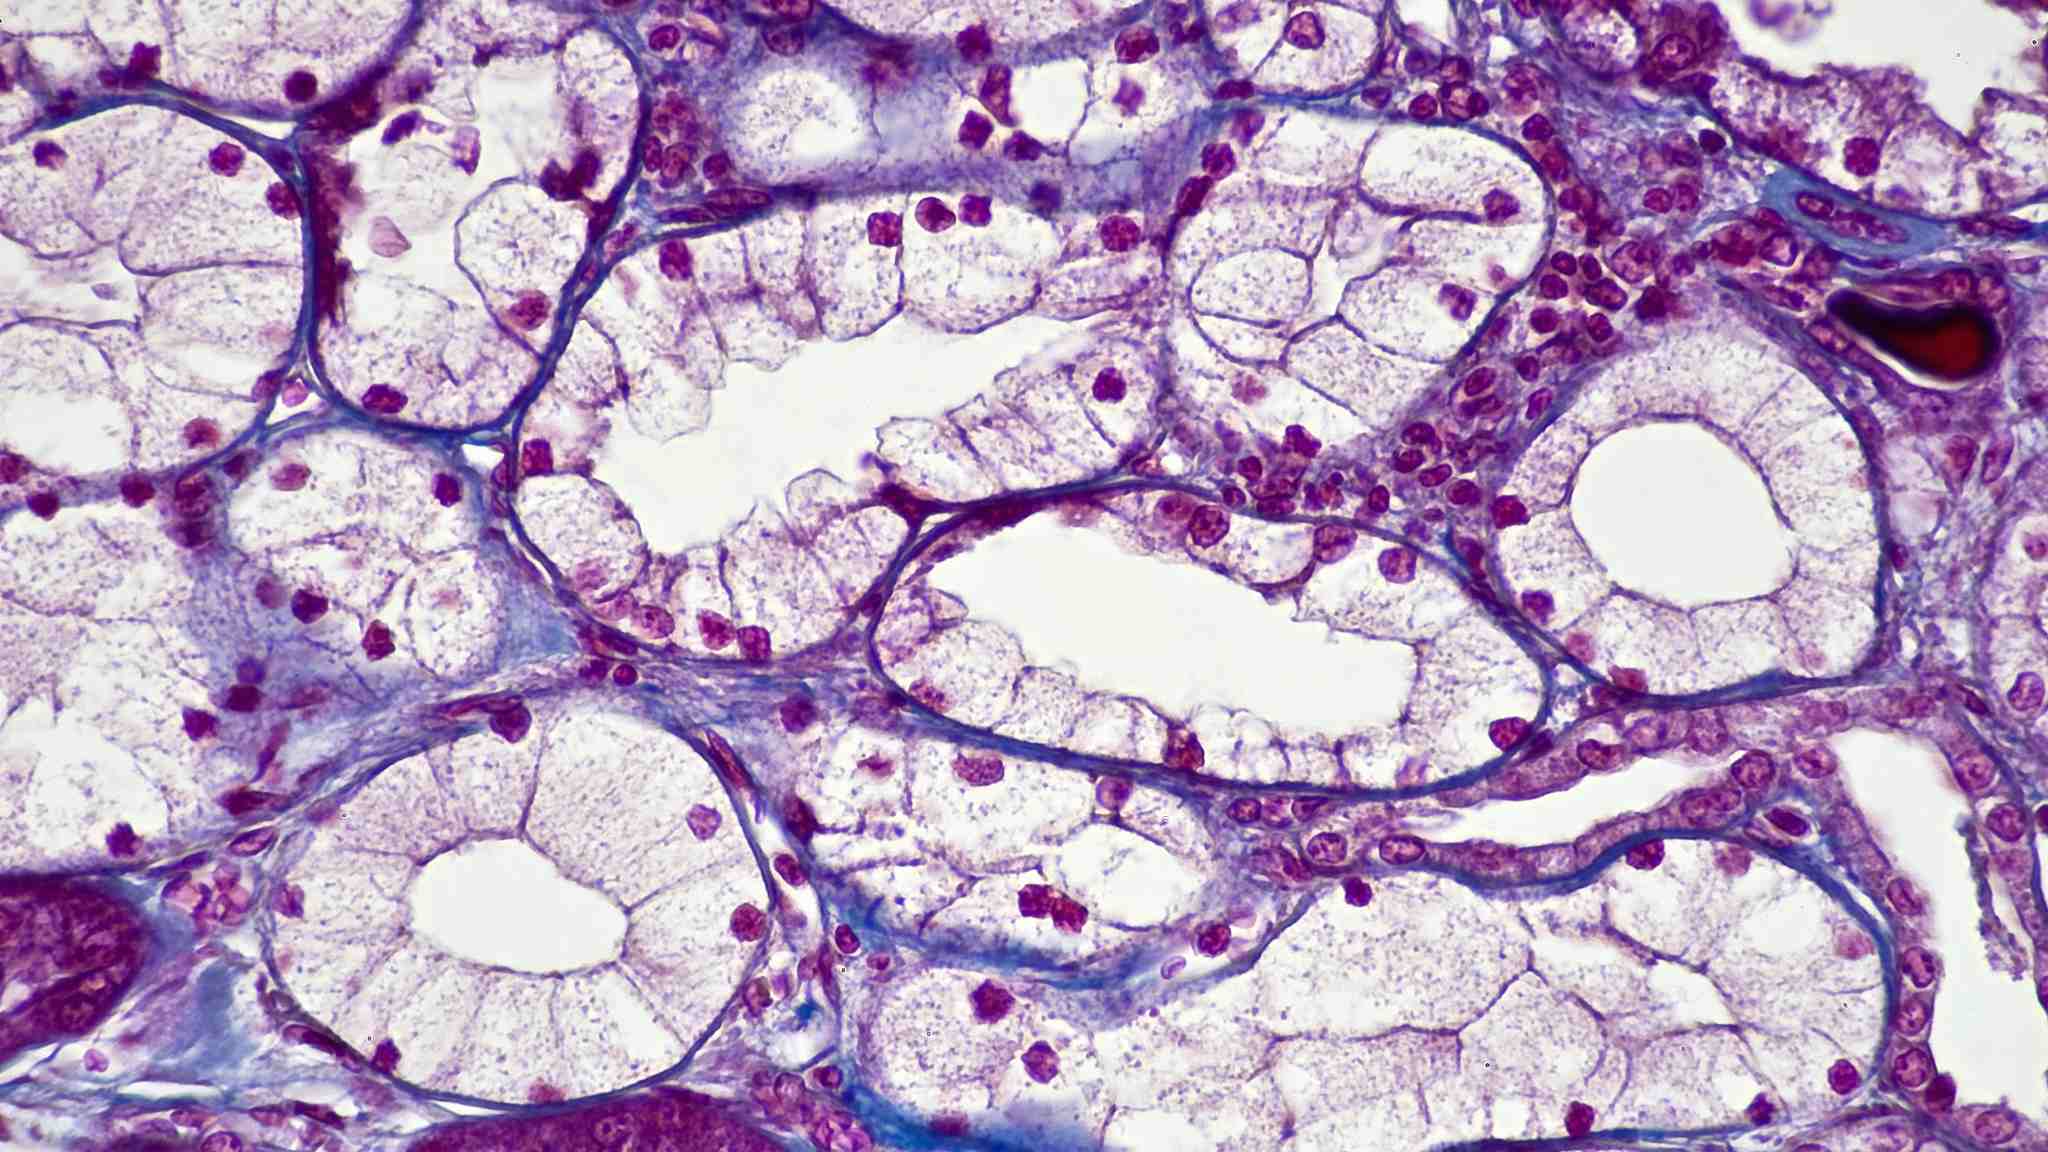

A microscope photo shows simple cuboidal epithelium forming kidney tubules. /VCG Photo